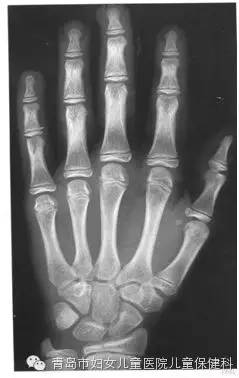

如何測骨齡?

拍一張左手的正位片,由專業(yè)的醫(yī)生應(yīng)用電腦軟件進行測評。根據(jù)骨齡預(yù)測身高是體育界選材廣泛應(yīng)用的成熟的技術(shù)。